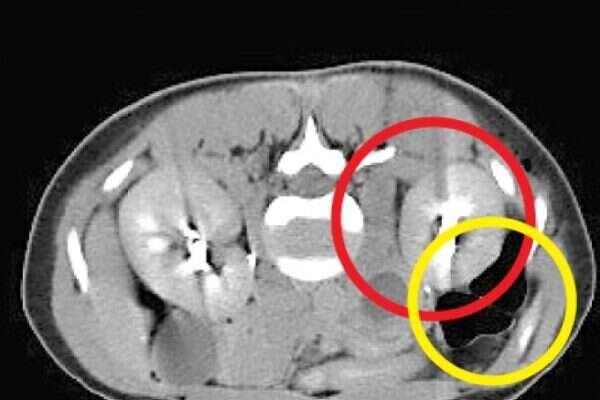

הרופא לא האמין למראה בדיקת האולטרסאונד: תוצאות בדיקות המעבדה הראו שבתום טיפולי הפריה של מטופלת הושג הריון, אך בבדיקת ההדמיה לא נראה עובר בחלל הרחם. הסיפור המיוחד התרחש בבית החולים הדסה, שם טיפלו באזרחית קפריסאית (30) שנשאה הריון נדיר במיוחד. העובר לא היה ברחם שלה וגם לא בחצוצרות, מקום שבו בדרך כלל משתרשים הריונות מחוץ לרחם. בבדיקת האולטרסאונד נמצא שההריון השתרש בין הכליה לבין כלי דם גדול שמוביל אליה. מדובר בדיווח השני בעולם על מקרה שכזה. "הרופא שליווה את ההריון בקפריסין יצר איתנו קשר והמלצנו לו להטיס את האישה אלינו", אמר פרופ' נרי לאופר, מנהל המערך למיילדות ולגינקולוגיה בבית החולים הדסה, "הריון כזה עלול לסכן את חייה של האישה באופן מיידי. השליה של העובר חודרת לתוך כלי הדם הגדול ועלול היה להיווצר מצב שאבי העורקים של אותה אישה היה מתפוצץ בחלל הבטן וגורם למותה". בהדסה התגייסו להטיס את האישה לארץ באמצעות "אמבולנס מעופף" - מסוק עם ציוד רפואי וליווי רפואי שנמצא בבית החולים הירושלמי. לדברי פרופ' לאופר, אי אפשר היה להמשיך את ההריון הזה בשל הסיכון הרב לחיי האישה ולכן הוחלט לבצע הפסקת הריון: "לאחר ביצוע הפסקת ההריון ראינו דם בכמות גדולה שהצטבר מתחת לכליה. קראנו לכירורגים מומחים לכלי דם משום שהיה חשש שהאישה תאבד את הכליה. למרות הזרקת חומר שחוסם את כלי הדם האישה המשיכה לדמם והוכנסה לחדר ניתוח. קיבצנו כמות גדולה של רופאים מומחים, רנטגנולוגים, כירורגים כלליים וכירורגים של כלי דם ובמהלך הפעולה - שנמשכה 48 שעות ברצף - התברר לנו שההריון כבר חדר לכלי דם גדולים". בסופו של דבר הצליחו המנתחים לסגור את כלי הדם מעל ומתחת למקום שבו השתרשה השליה והתפתח ההריון, ולהציל את חייה של האישה בלי לפגוע בכליה שלה. במהלך הניתוח התבררה עובדה מעניינת נוספת - העובר ניקב את ציפוי הבטן ולמעשה חדר לאחוריו. לדברי פרופ' לאופר, "זהו מקרה מאוד נדיר. השכיחות של הריון מחוץ לרחם נעה בין חצי אחוז לאחוז בודד, אך בהריונות שהושגו בהפריה חוץ גופית היא גבוהה יותר ועומדת על 5-2 אחוזים. רוב ההריונות שמחוץ לרחם נמצאים בחצוצרה ונדיר ביותר שהריון יימצא בחלל הבטן. לצערי, לא היה אפשרי במקרה הזה להציל את ההריון, אך אני שמח שאפשר היה להציל את האישה".

הריון נדיר: העובר התמקם מתחת לכליה

מקרה שני מסוגו בעולם טופל בהדסה • אזרחית קפריסין שנשאה עובר מחוץ לרחם הוטסה לארץ • הרופאים נאלצו להפסיק את ההריון כדי להציל את חיי האישה